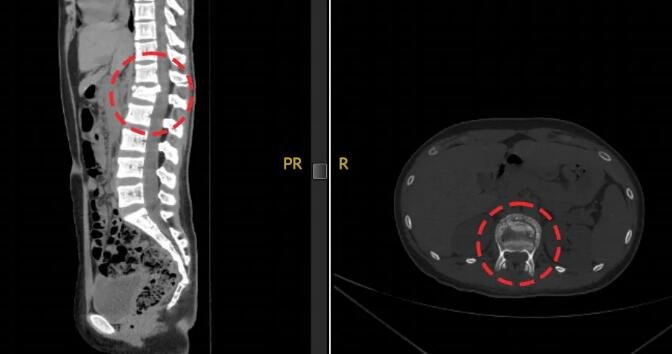

△小蕊腰椎伤处透视影像

经检查,小蕊腰椎前、中、后三柱均有骨折,双侧足踝粉碎性骨折,尤其是左踝距骨碎成了很多块。这个爱打篮球的姑娘,面临后半生行走困难的危险。